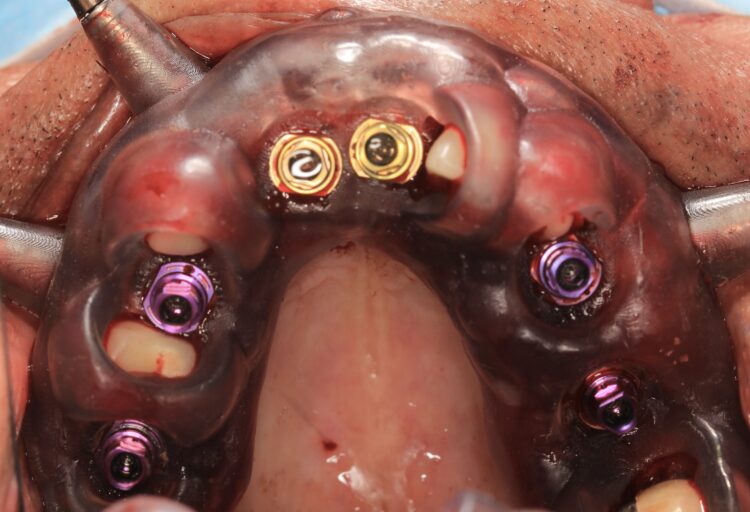

The implant beds were then prepared with the surgical guide in situ. Six CONELOG® Progressive-Line implants from BioHorizons Camlog were placed in accordance with the predetermined positions, depths and angulations. These implants were selected for this case because they feature an optimal thread design and tapered figure, promoting high primary stability – which is essential in full arch reconstruction cases.

The implants were placed through the guide for better accuracy and precision. A surgical primary stability of >35Ncm was achieved for each implant. Once the implants were placed, the surgical guide was removed, and the extraction of the remaining teeth was completed.

In preparation for the provisional prosthesis, straight multi-unit abutments were fitted onto the implants and torqued to 25Ncm, followed by titanium cylinders. For the anterior implants in the areas of the central incisors, the Comfour Straight bar abutments were used. The narrow prosthetic platform of these Comfour abutments (4.3mm) compared to the wider prosthetic platform of the standard multi-unit abutments is advantageous as it provides more space for soft tissue thickness and stability of the therapeutic outcome in the long-run.